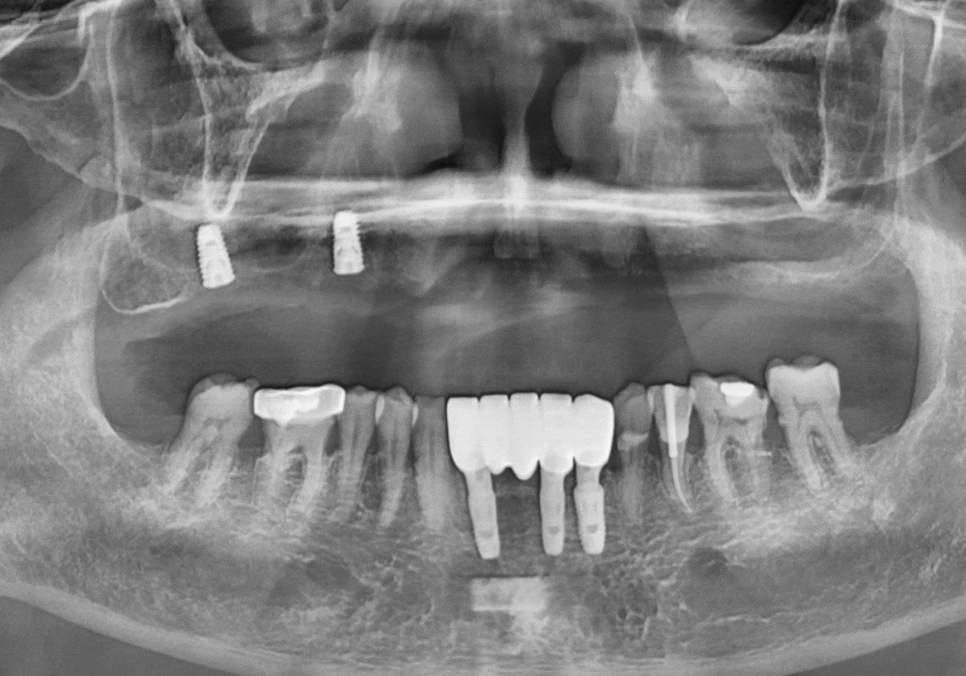

방사선 사진을 보니

잇몸뼈가 전체적으로 아주 얇아져 있었죠.

전체적으로 뼈가 얇았기에,

CT 정밀 분석을 통해

그나마 뼈 상태가 양호한 부위를

전략적으로 선택했습니다.

총 6개의 임플란트를 심고

보철로 연결해 12개의 치아를

만드는 계획을 세웠죠.